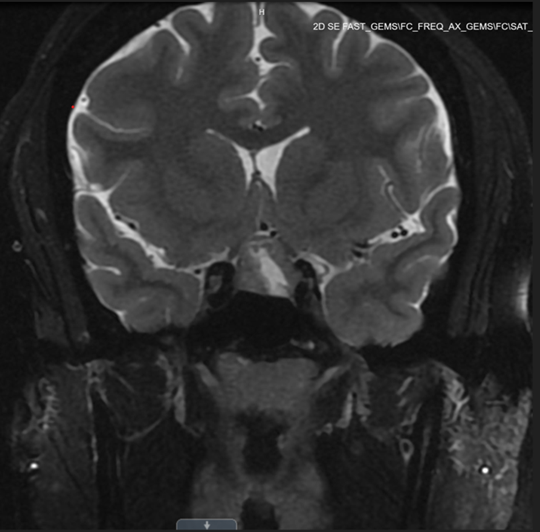

Following her visit to a gynecology clinic, the patient underwent a comprehensive evaluation for amenorrhea (Tables 1 and 2). Work-up revealed elevated prolactin levels, measuring 74 ng/mL (3.34–26.72 ng/mL) in addition to a markedly elevated ACTH level of 105 pg/mL (reference range, 7.2–63.3 pg/mL) One week before surgery, free cortisol was within the normal range (1.46 µg/dL); and total cortisol was not measured preoperatively (Table 2). A subsequent magnetic resonance imaging (MRI) brain revealed a 1.2 x 1.5 x 1.6 cm heterogeneously enhancing pituitary macroadenoma, characterized by a central cystic/necrotic component (Figure 1). The imaging demonstrated mass effect on the optic chiasm and slight extension into the left cavernous sinus, accompanied by a mildly thickened pituitary stalk. As a result, the patient was referred to neurosurgery for surgical intervention.

Figure 1. Preoperative pituitary MRI showing pituitary macroadenoma.